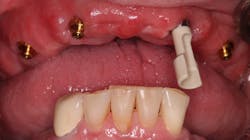

Fixed implant-supported bridges are becoming more prevalent worldwide. There are multiple types of bridges available, but all are expensive, and they require advanced clinical skills. Although these fixed bridges are a wonderful service to offer, we should remember the value of removable implant-retained dentures (figure 1). Attachments, such as Locator by Zest and Equator by Rhein83, have many benefits. They are the most affordable, least complicated, easiest to repair, and easiest to clean full-arch implant option.

Tip no. 3: Use more implants

It is widely noted that a minimum of two implants are required in the mandible for removable dentures.5 Four or more implants are optimal for the maxilla.6 These minimums can be successful more than 85% of the time, but long-term success can be increased by adding additional implants (figure 4).7 Balaguer et al. studied 95 patients over an average of six to nine years and found that survival rate in the maxilla of four implants was 85.7%. Survival rate of six implants was 100%. In the mandible, survival rate of two implants was 96.6%, whereas survival rate for three implants was 100% and survival rate for four implants was 99%.7

Adding additional implants reduces stress on each individual implant. In most cases, it helps ensure that if an implant is lost, there will be enough remaining implants for a successful case. In the mandible, additional implants will increase retention and, therefore, patient satisfaction. We offer financial incentives for our patients to add additional implants. It’s a win-win. Our patients enjoy greater security and success, and we invest less clinical time on adjustments and addressing complications.